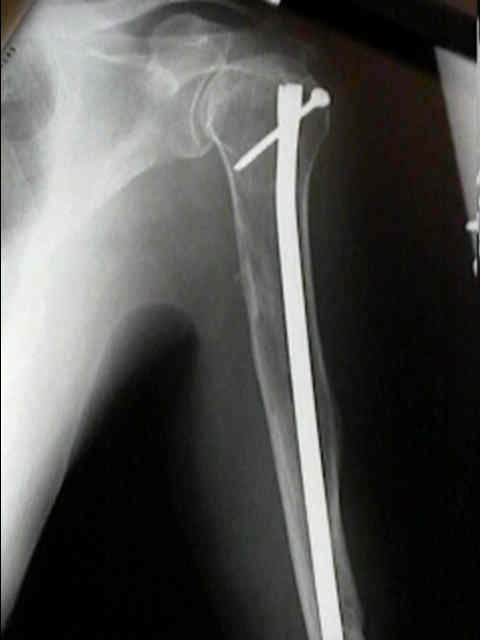

Surgical Fixation

- Treatment of pathologic fracture of the humerus.